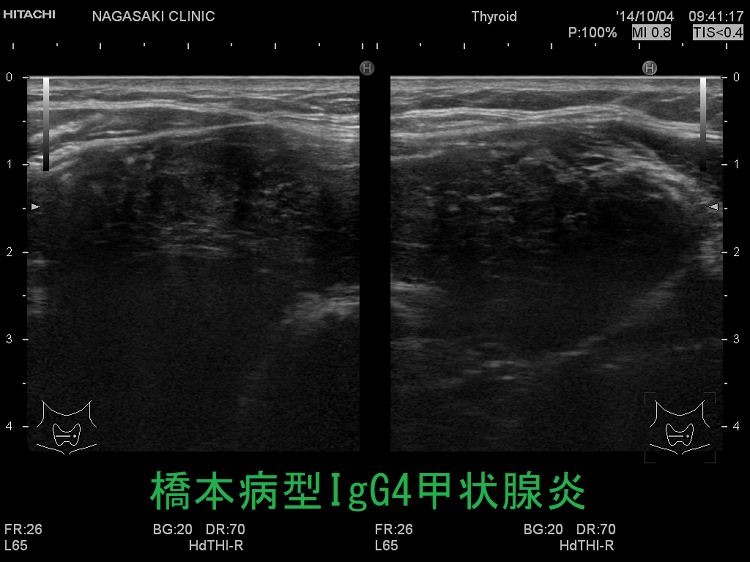

IgG4甲状腺炎(橋本病型IgG4甲状腺炎)IgG4関連甲状腺炎は、線維化が著明な白黒画像(Bモード画像)に加え、エラストグラフィーによる硬さの評価が役に立ちます。

IgG4甲状腺炎(橋本病型IgG4甲状腺炎) 超音波(エコー)画像

橋本病型IgG4甲状腺炎 エラストグラフィー

IgG4甲状腺炎(橋本病型IgG4甲状腺炎) 超音波(エコー)画像 エラストグラフィー;線維化した部分はエラストグラフィー青く(硬く)見えます。